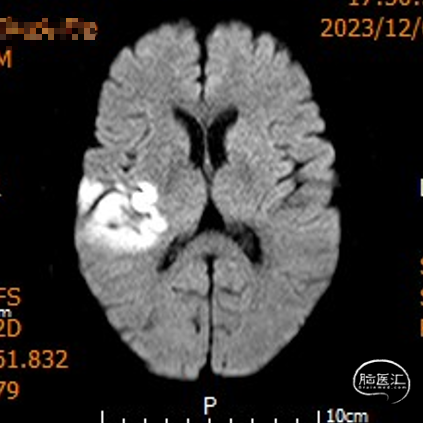

影像信息

颅脑CT示:

1.双侧侧脑室旁及右侧额顶叶多发脑梗死;

2.脑白质变性。

MRI示右侧颞顶叶及胼胝体急性脑梗死。